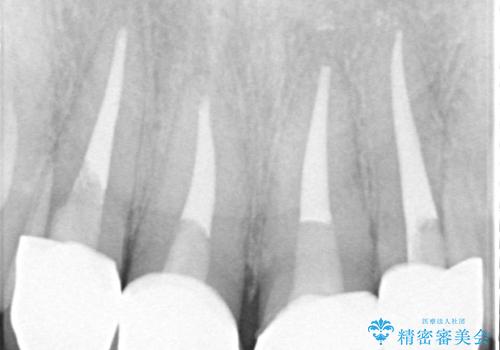

- 以前他院で治療を行った前歯の被せものが欠けてしまい、きれいなセラミックにしたいと来院された患者様です。

人工物のような印象が強くあまり自然とは言えない状態でした。

また被せものと土台の間に隙間があり、適合もよくない状態でした。